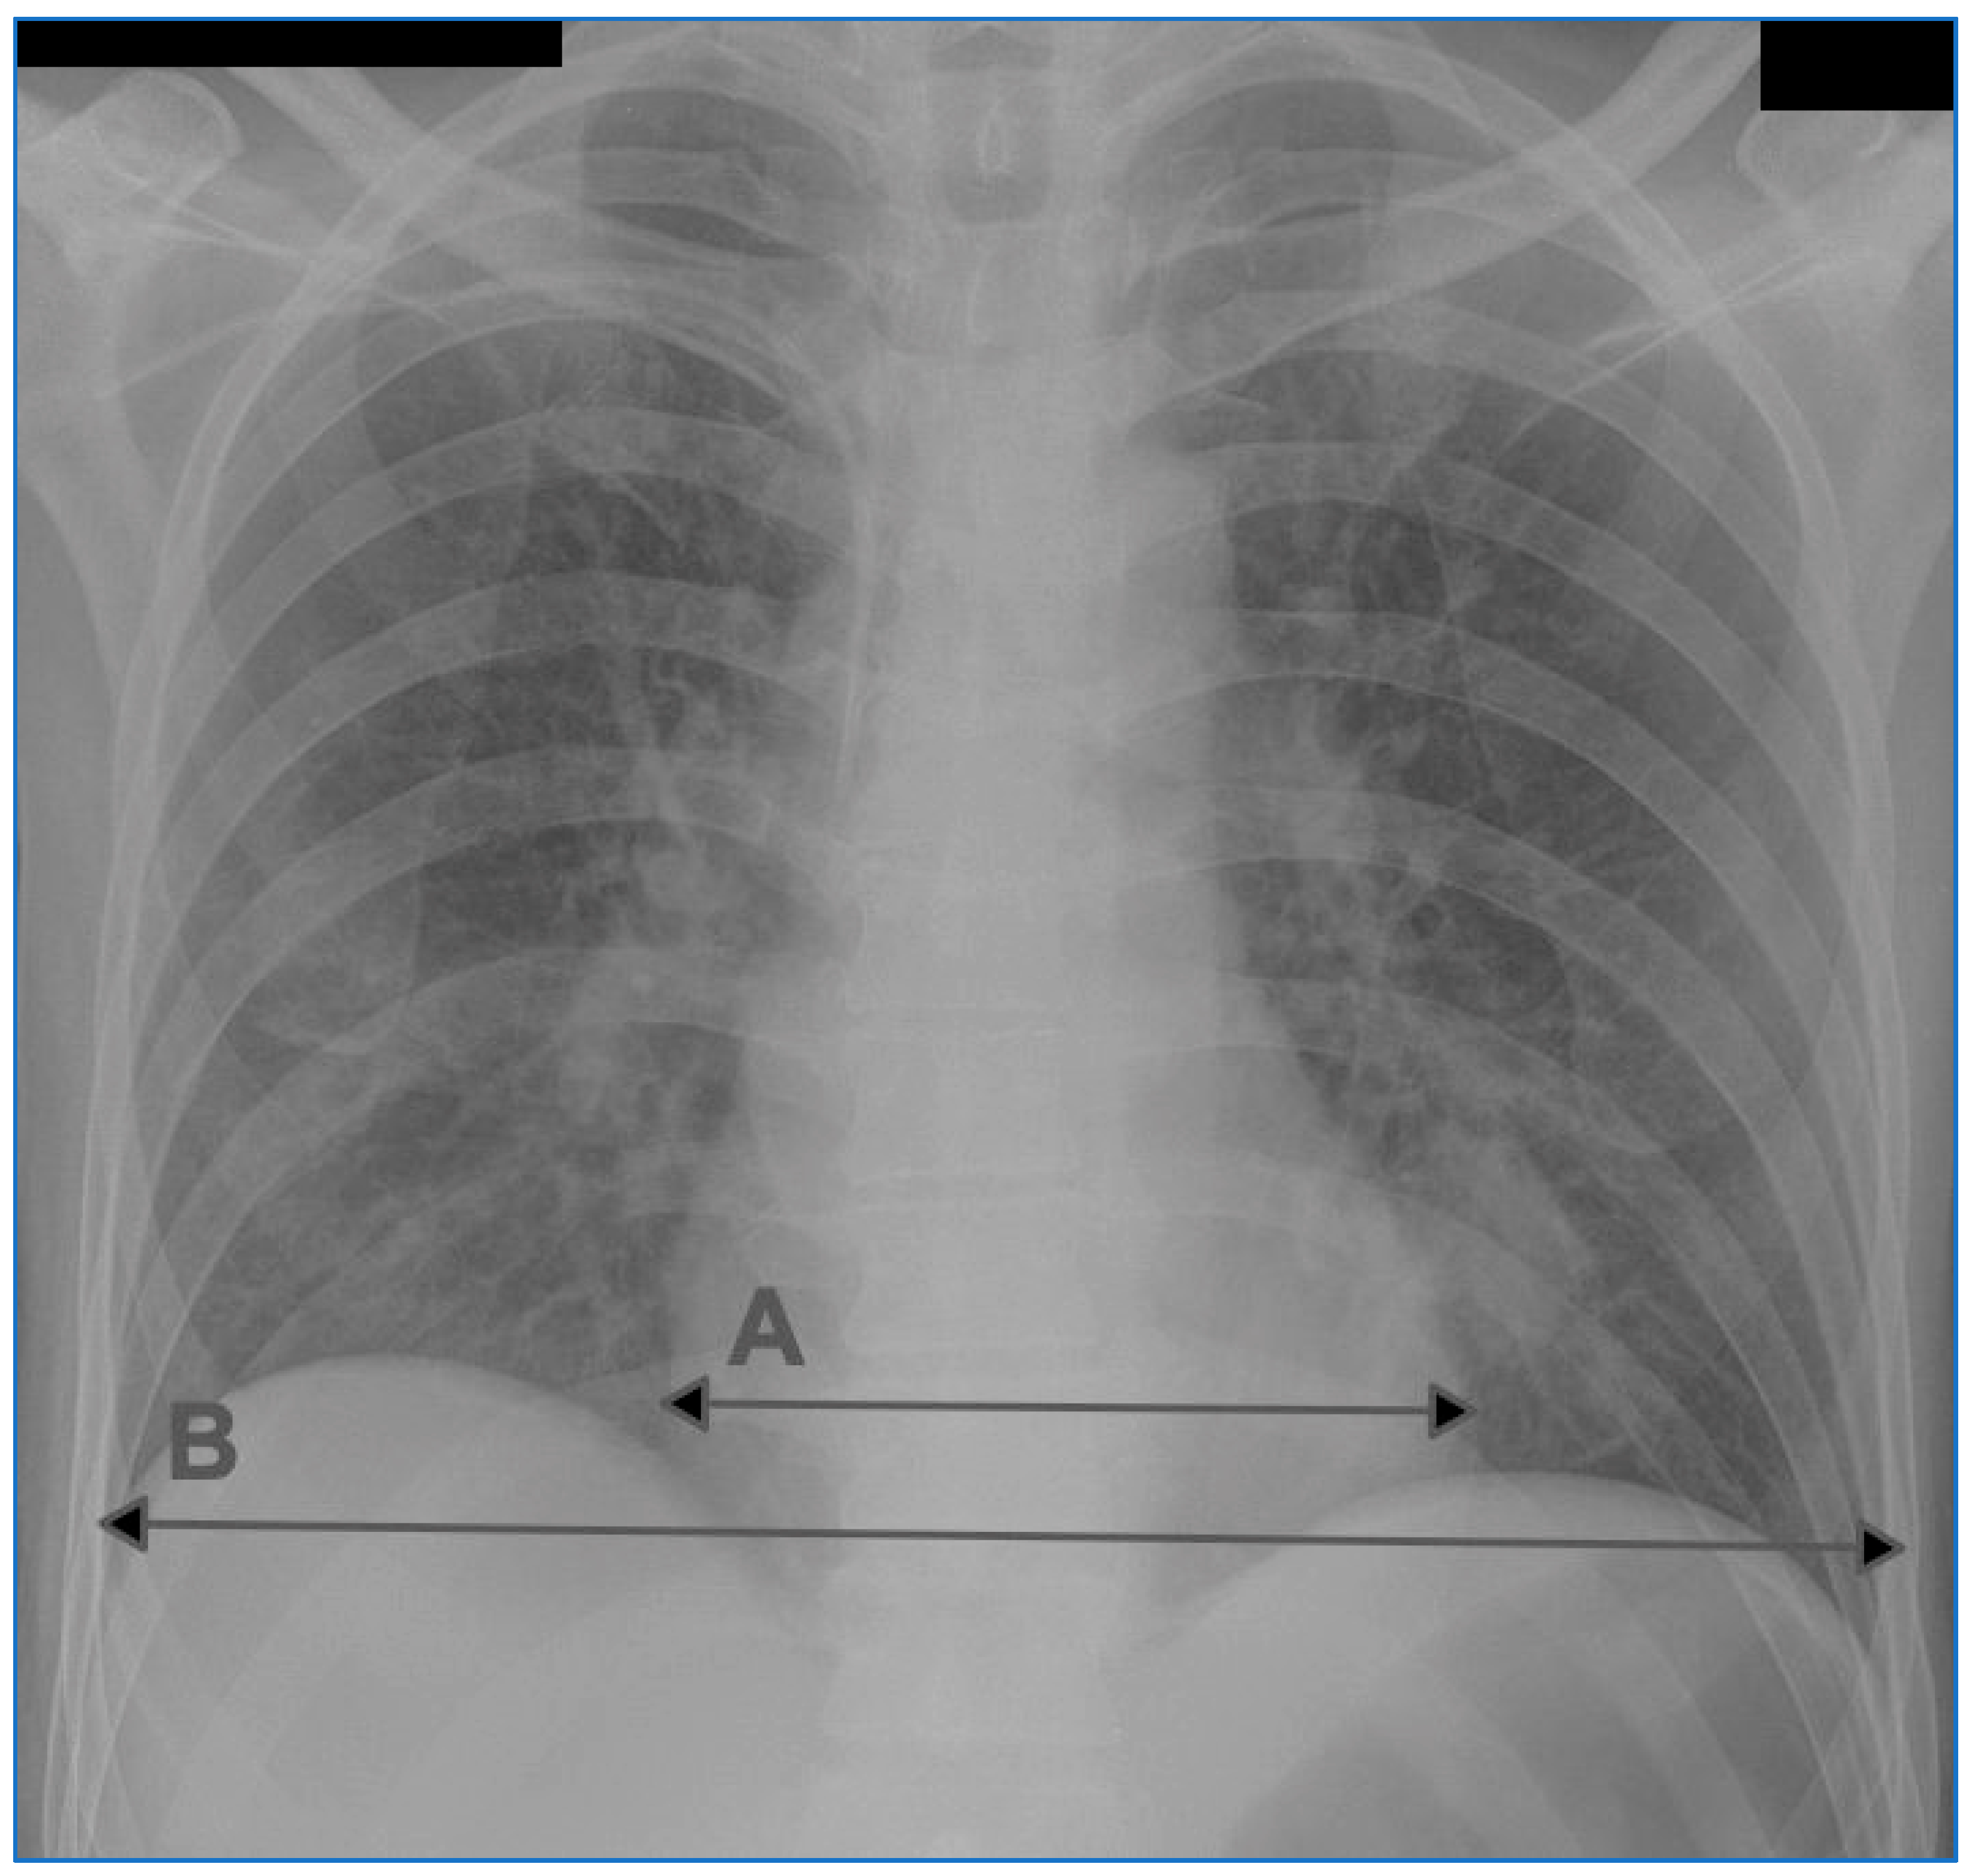

| enlargement of the heart silhouette | cardiothoracic ratio (CTR) on chest radiograph in antero-posterior projection > 0.55 | G: enlarged heart silhouette (CTR > 0.55) H: non-enlarged heart silhouette (CTR ≤ 0.55) | G: 37 H: 24 |

| C width [mm] | 189.10 | 27.61 |

| T width [mm] | 331.59 | 33.61 |

| CTR | 0.57 | 0.05 |